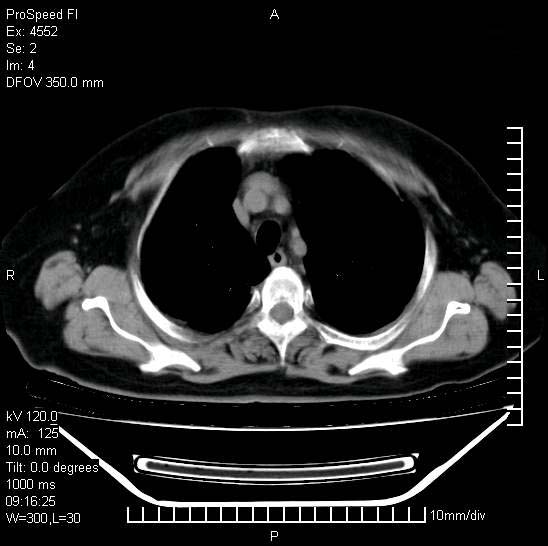

标题: CT15528:女性,79岁,近几日晚上高热,39度,仍咳少量血 [打印本页]

十几年前曾患肺结核,一周前突咳血约100ml,中性粒细胞稍高,诊断两上肺陈旧结核,下肺炎症,给予抗炎治疗,近几日晚上高热,39度,仍咳少量血,4天前ct及今天ct上传。

[face=黑体]8月30日[/face]